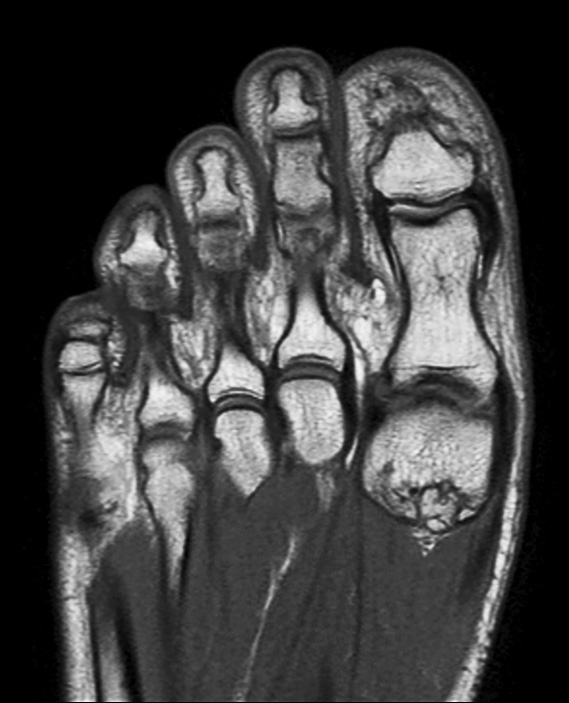

Coronal PDw mDIXON TSE  (water only)

-